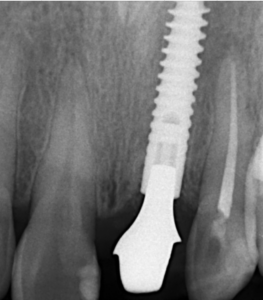

위의 사례에 해당하는 임플란트 엑스레이 사진입니다. 보시다시피 뼈손실이 전혀없이 잘 유지되고 있습니다. 앞니에는 독일 앵킬로스가 정말 좋은 결과를 가지고 있습니다. 2000년도에 시술하신 분들도 최근에 방문해서 확인한 바 처음 시술했을 당시와 유사하거나 오히려 더 자연스럽게 보철이 유지되고 있었으며, 뼈는 처음보다 더 충분히 리모델링이 일어나 안정감을 볼 수 있었습니다.

초창기에 개발되었던 외부결합형 임플란트보다는

내부결합형의 locking형태가 보다 안정적인 앞니의 잇몸라인을 보장한다고 말할 수 있습니다.

잇몸의 양의 더 풍부하고 또한 뼈의 소실이 거의 없어

장기적으로 안정적인 모양을 유지할 수 있다는 장점이 있습니다.